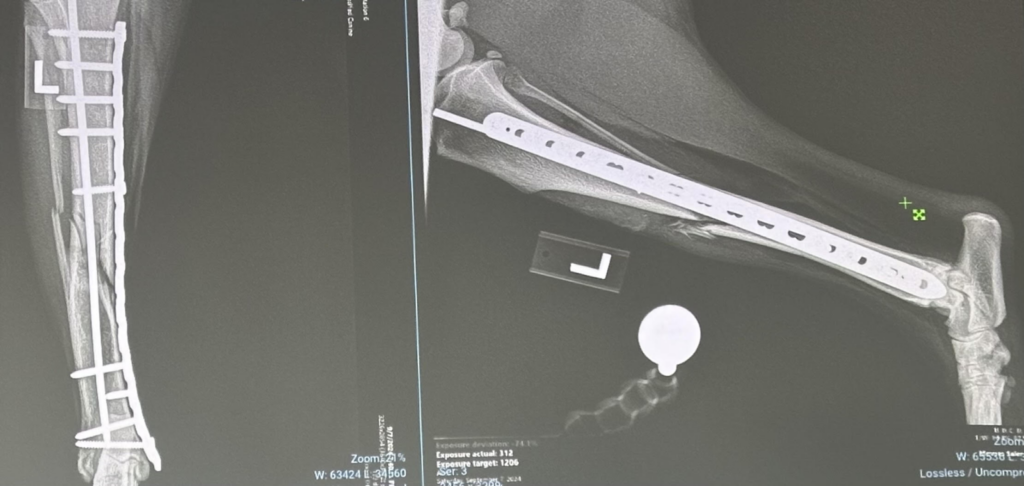

TPLO Surgery: Advanced Knee Repair for Your Dog

Is your dog limping or holding up a hind leg? A torn Cranial Cruciate Ligament (CCL)—similar to an ACL tear in humans—is one of the most common orthopedic injuries in dogs. At Lethbridge Pet Hospital, we offer TPLO (Tibial Plateau Leveling Osteotomy) surgery, the gold-standard treatment for stabilizing the knee and getting your pet back to their active self.

Our surgical team uses state-of-the-art orthopedic equipment and precise techniques to ensure the best possible outcome. Every TPLO procedure at our clinic includes: